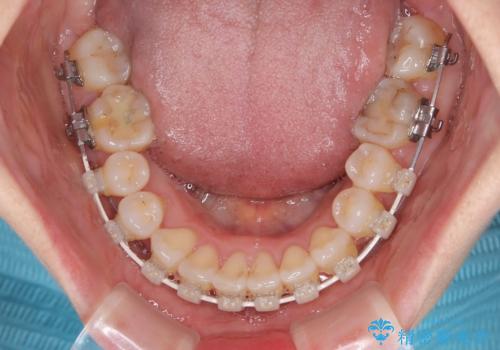

- 審美装置

- 2年1ヶ月

- 10-30回